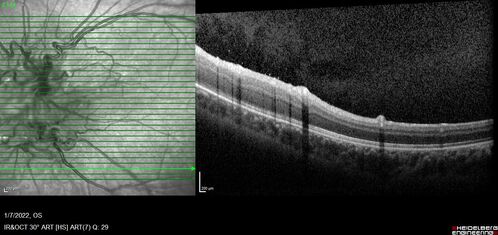

Combined hamartoma of the retina and retinal pigment epithelium

8 year old boy failed vision screening at school. VA 20/20 OD, 20/40 OS

Combined hamartoma of the retina and the retinal pigment epithelium